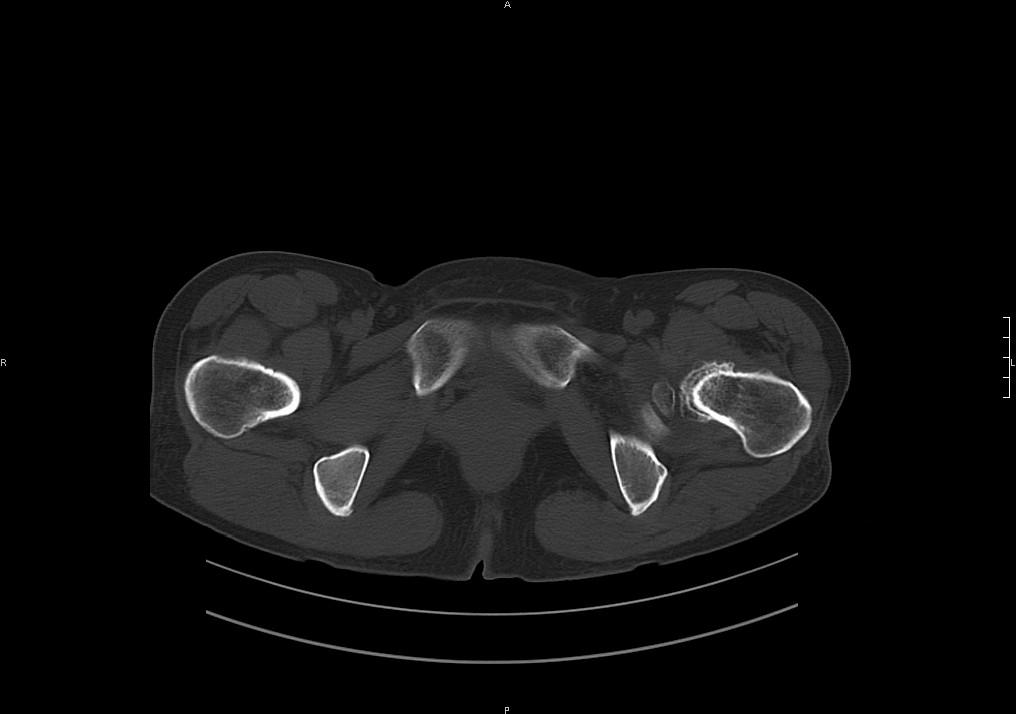

支持陈旧性骨折,结合病史加重一个月,考虑缺血性坏死初期。

股骨颈陈旧性骨折

髋关节退行性骨关节病

陈旧性骨折